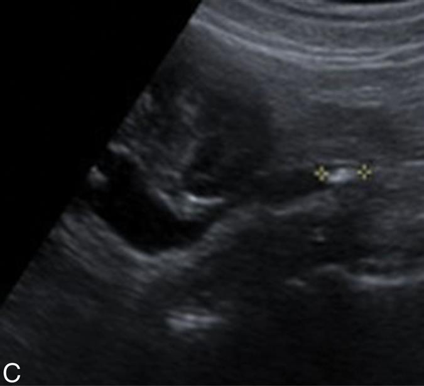

Splenic hematoma: Small hypoechoic separation medial to the splenic capsule represents a splenic hematoma.

Splenic hematoma: Separation of the splenic capsule from the spleen secondary to a large hematoma resulting from an automobile accident.